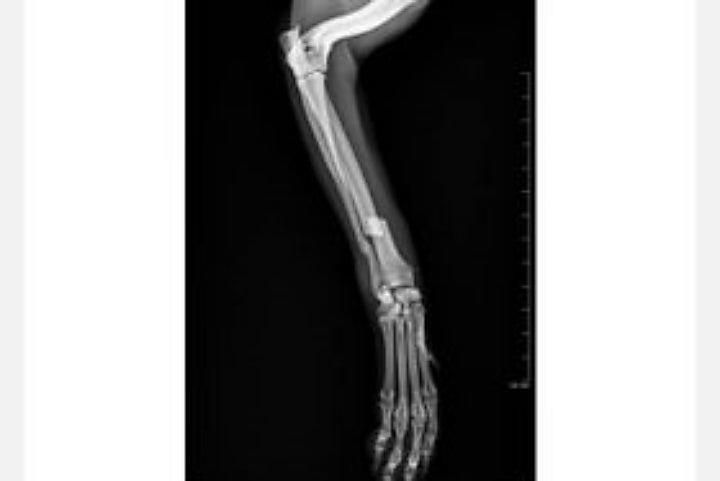

O cachorro foi encaminhado à Clínica Escola Veterinária da Unipar e após exames e consulta, foi diagnosticada fratura no rádio e na ulna, necessitando assim de uma cirurgia ortopédica.